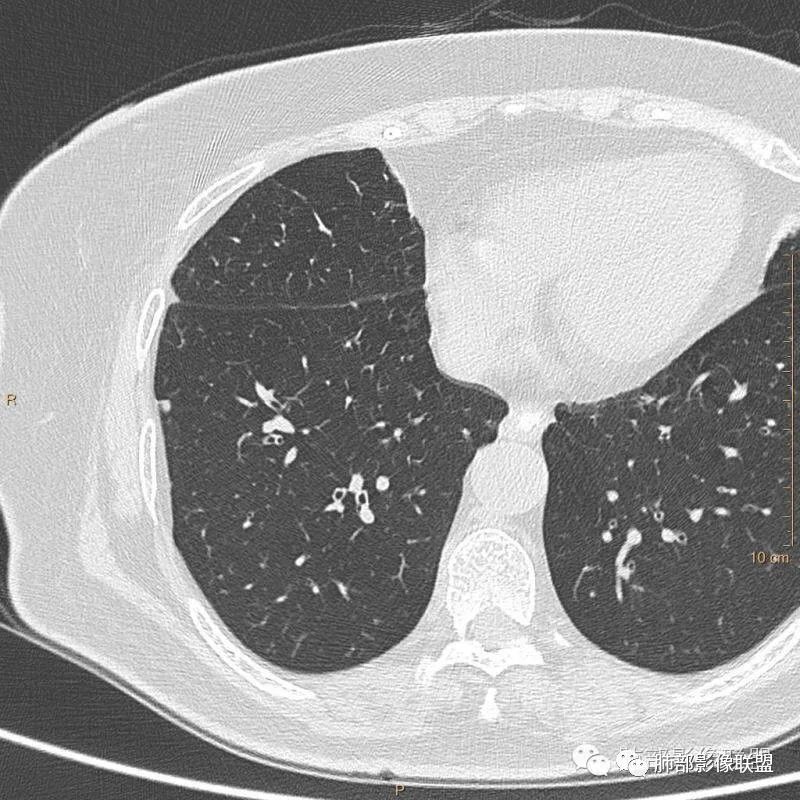

病例二:

以上病例,有什么共同点?1、病灶均位于胸膜下或叶间胸膜下;

2、病灶边缘多平直,大部分呈三角形,部分呈椭圆形;

3、病灶边缘见一条或数条细线与胸膜相连。

正常情况下,肺内淋巴结是不显示的,一般是慢性炎症所致,老年人和吸烟者多见。影像上常见于胸膜或叶间胸膜下,迄今为止,所有的报道均距胸膜或叶间胸膜小于2.0cm以内。也可以表现为与胸膜或叶间胸膜相贴的结节。绝大多数位于中下叶(气管隆突水平以下),上叶也可见到,但较少见。

长径均小于12mm。典型的形状为三角形,也可以为梭形、圆形或椭圆形。诊断的关键在于见到1-5条细线与胸膜、叶间胸膜或静脉相连,有时状如坐落于电路板的“二极管”,但以薄层CT显示为佳。有作者病理对照线状影为小叶间隔,有作者病理对照为淋巴管。其实不矛盾,因为淋巴管走行于小叶间隔内。